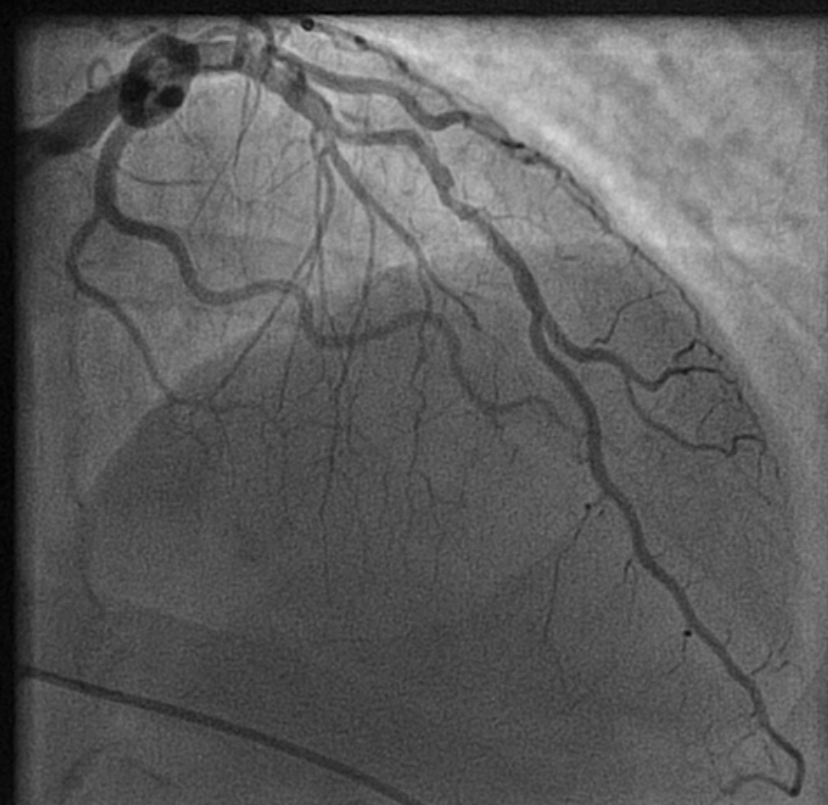

How to tackle this stress positive Intermediate LAD lesion. Functional capacity good. Non-diabetic, mildly elevated lipids. Now, continuing medical management with intensive lipid control is the best possible management. (We have evidence for medical management being good even in significant 90% lesion) Above is a case report from https://www.acc.org/education-and-meetings/patient-case-quizzes/medical-therapy-for-cad